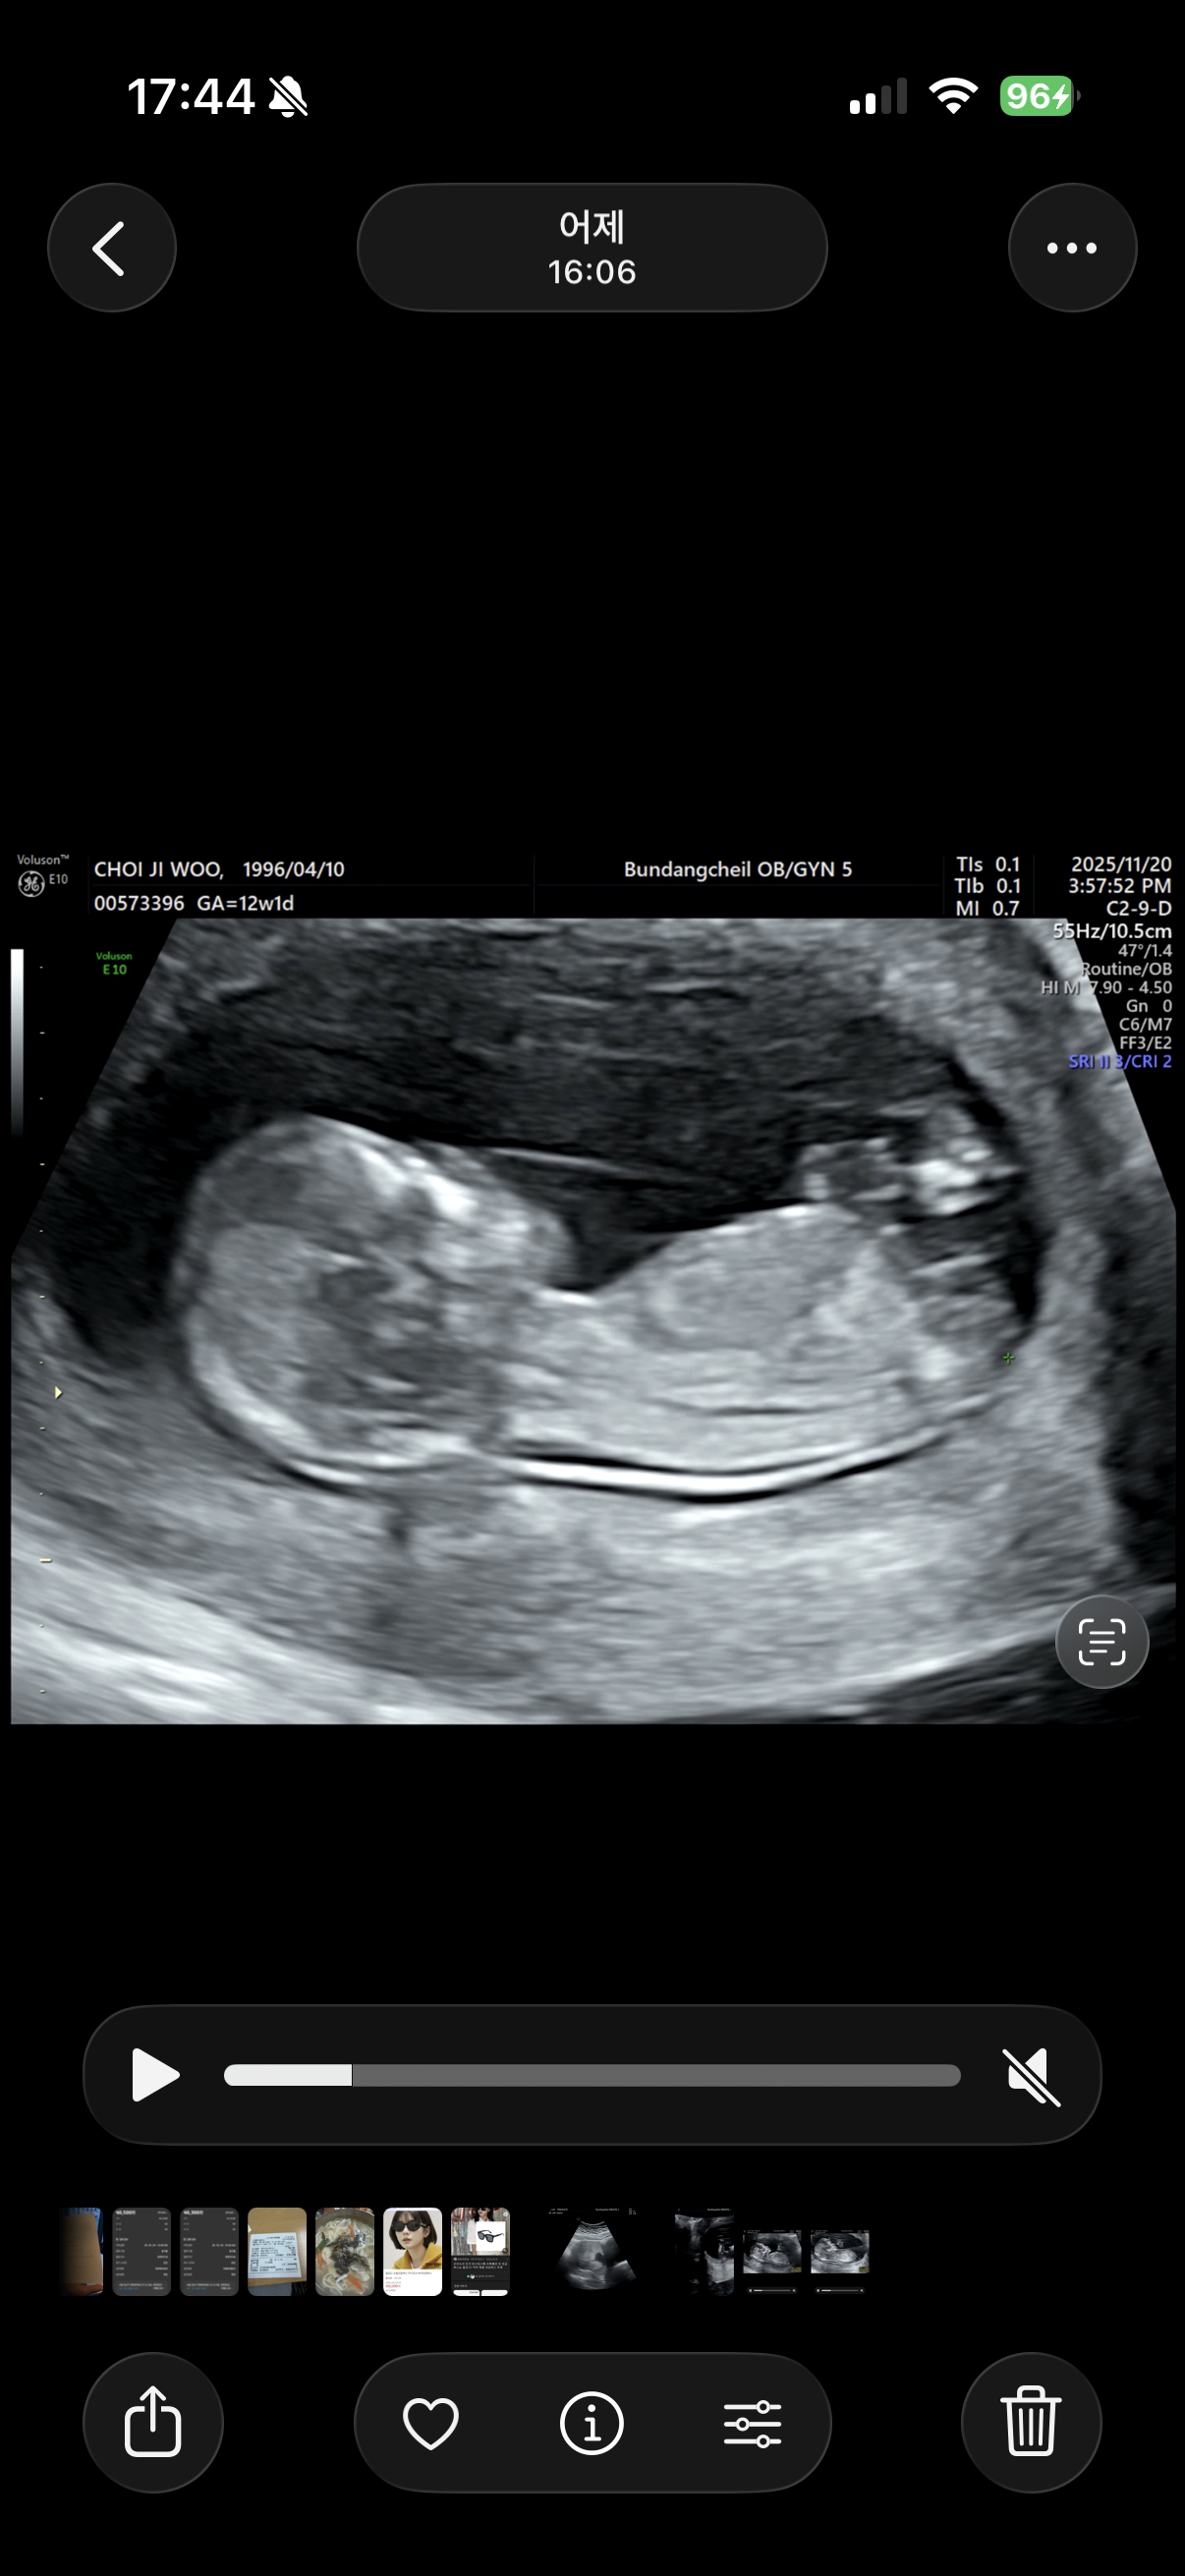

12주차 딸인지 아들인지 봐주세요 (각도법)

성별 참견 부탁두립니다